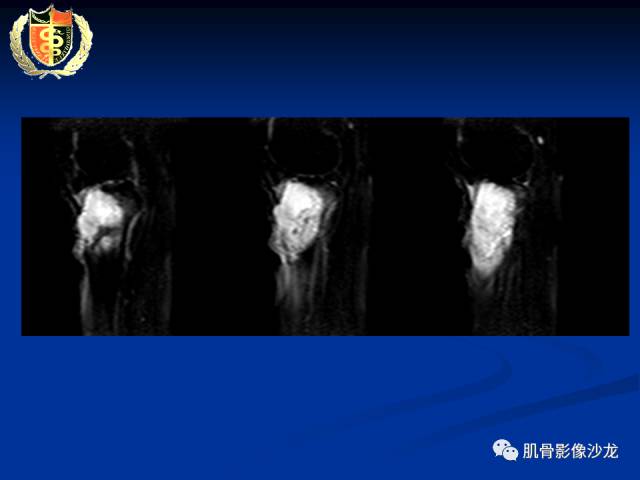

骨淋巴瘤及软骨肉瘤两例CT及MR影像表现

各位老师,磁共振图像是增强检查,最后一张是DWI图像[愉快]

胫骨近端骨质破坏,边缘不清,破坏边模糊,骨皮质不完整,可见软组织肿块突破骨皮质外,病灶累及关节面下,无关节内累及,MRI病灶呈T2WI高信号,信号均匀,考虑:恶性肿瘤性病变,淋巴瘤先考虑,转移瘤及其他待排

淋巴瘤弥散不受限吧

受限

内部密度和信号比较均匀,无钙化,无骨膜反应,骨质破坏边缘不清晰,软组织较明显,弥散受限,首先不能排除淋巴瘤